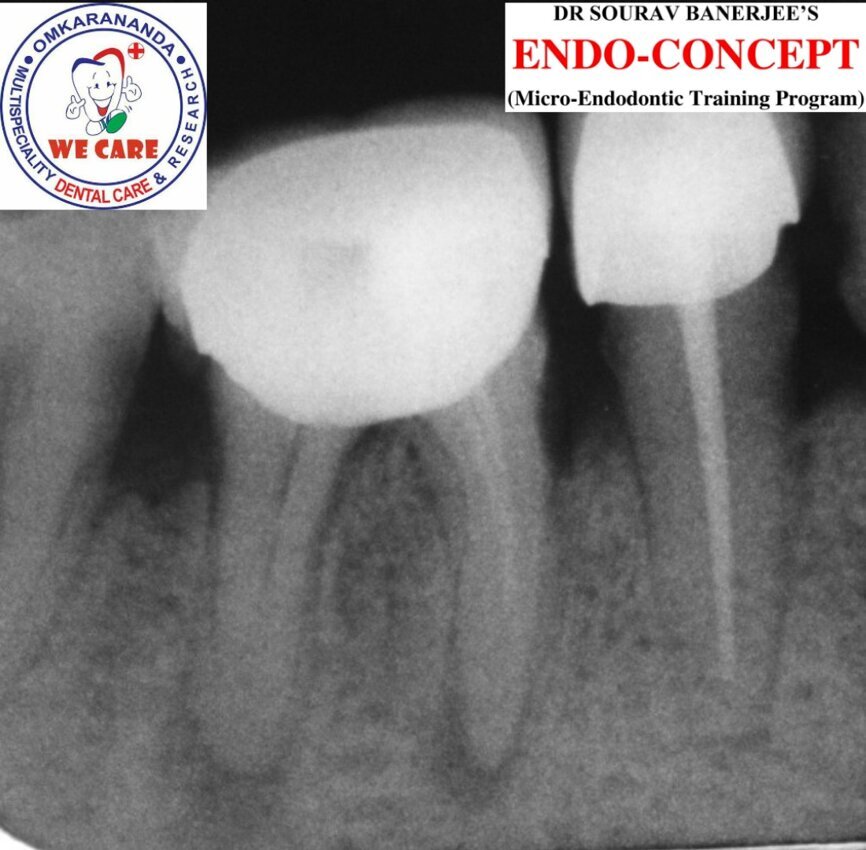

Fig.1a: Pre-op radiograph taken by the referring dentist.

Fig.1b: Pre-op radiograph taken by the author in relation to tooth #46 (January 2019).

When I had a close look at the preoperative radiograph from the referring dentist (Fig. 1a), I observed that there was insufficient obturation of the mesial canals and almost no obturation of the distal canal. Both roots displayed periapical radiolucency. The clinical examination revealed a Grade I mobility, and the tooth was tender to percussion. The periodontal examination ruled out any pockets and loss of attachment. We took an intra-oral periapical radiograph (Fig. 1b), from which we observed the loss of coronal structure and a large radiolucent area over the furcation area and the periapical area of both the mesial and the distal roots. A CBCT scan of tooth #46 was advised to check for any details that may have been missed in the intra-oral periapical radiograph (Figs. 2a–g). From the CBCT scan, it could be observed that there was inadequate obturation of the distal canal on the horizontal plane, no obturation beyond the middle third in the mesial canals and a breach of the floor of the pulp chamber. The questionable prognosis was explainedto the patient, and written consent was obtained.